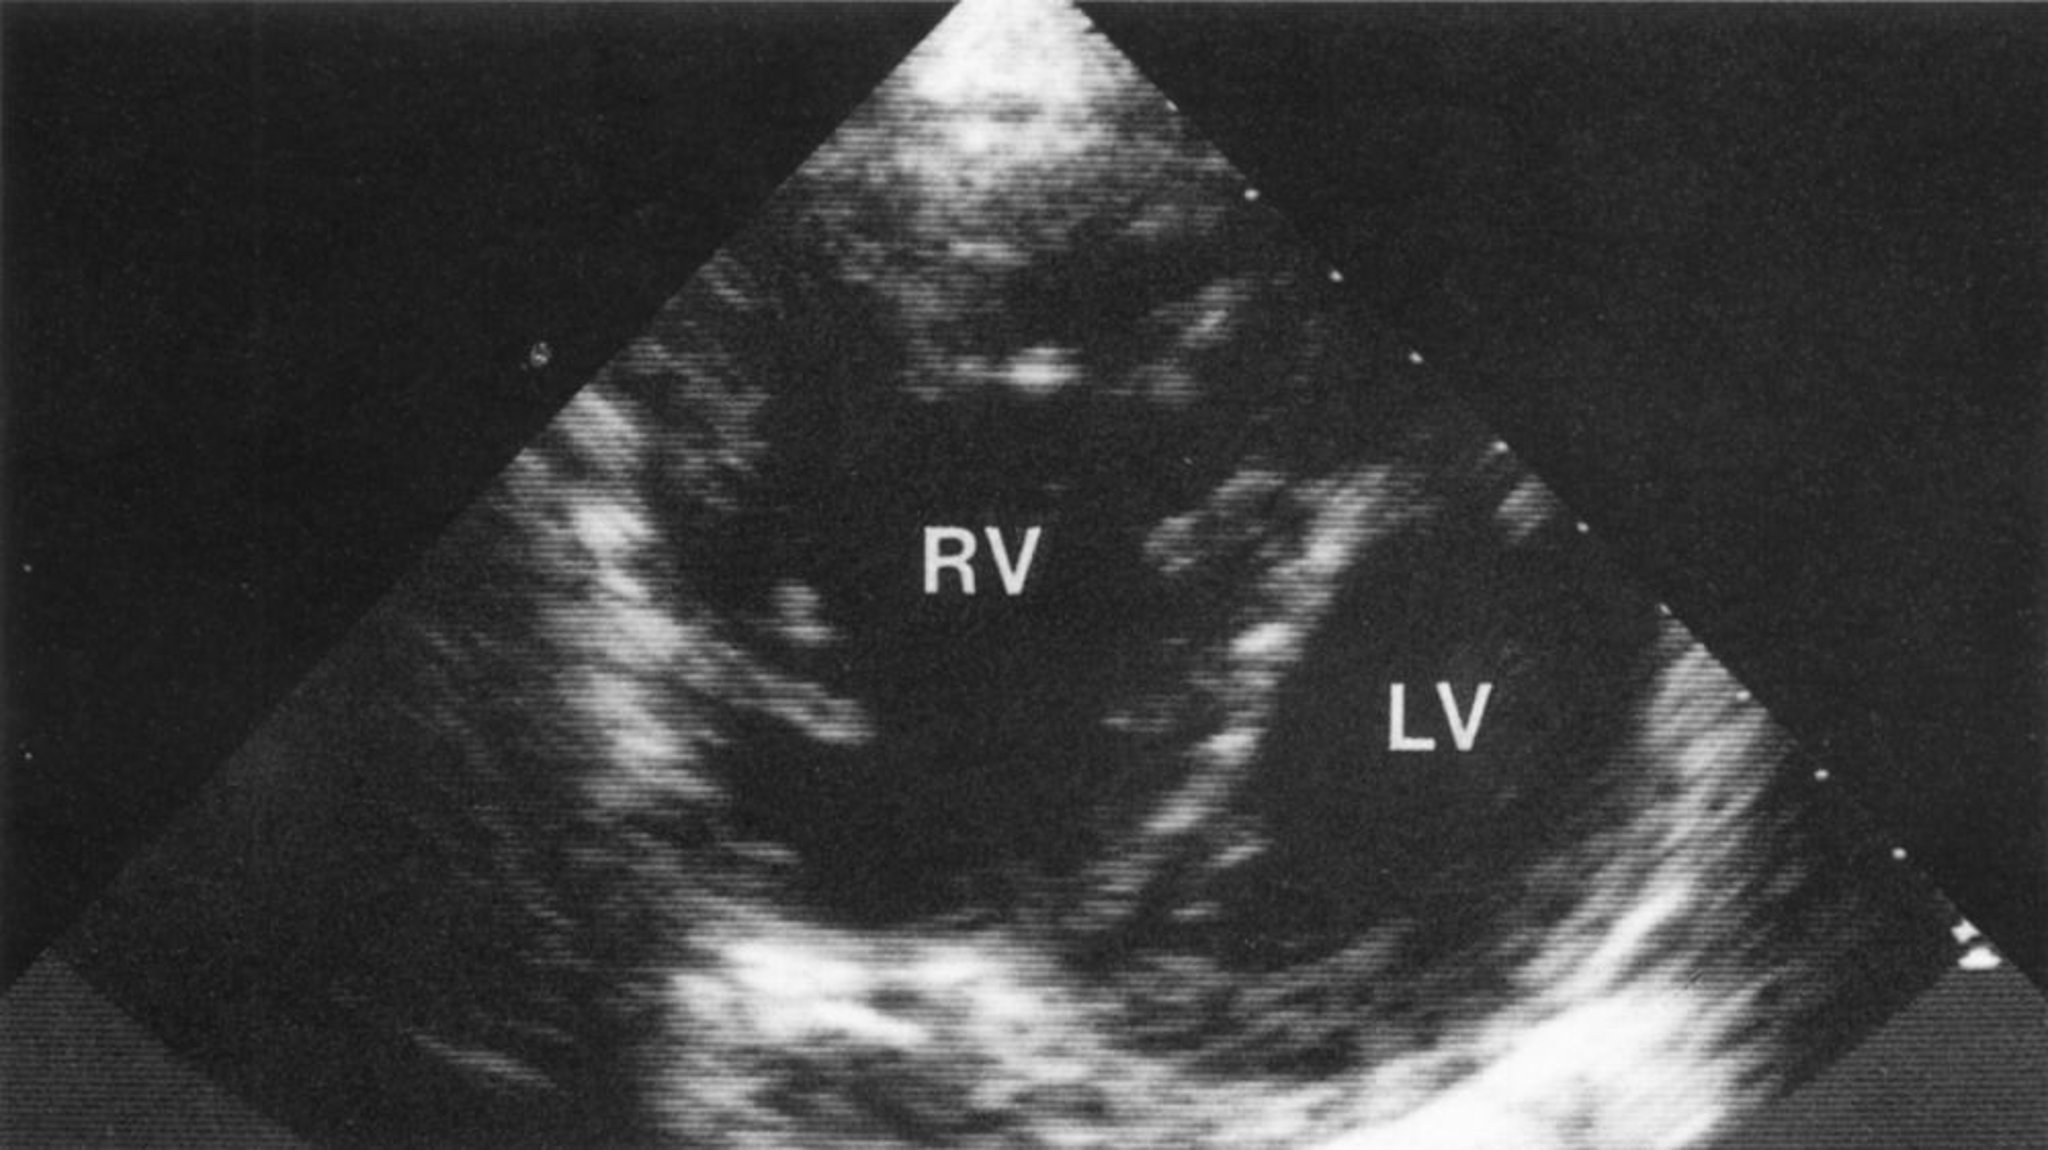

Cœur pulmonaire (échocardiogramme)

Vue en court axe montrant un ventricule droit nettement augmenté de volume avec hypertrophie du ventricule droit. Une courbure anormale du septum interventriculaire dans le ventricule gauche donne une configuration en D caractéristique du ventricule gauche, compatible avec une surcharge de volume et de pression du ventricule droit.